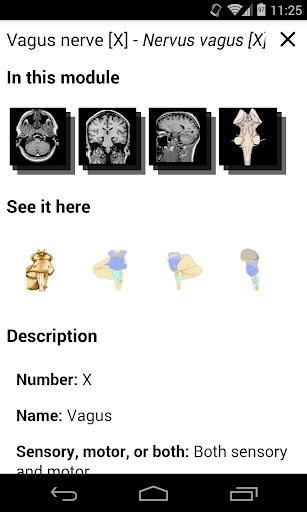

*Peningkatan tampilan detail bagian anatomi untuk memudahkan identifikasi dalam gambar modul saat ini dan modul lainnya.

tampilan detail istilah terkait struktur anatomi sekarang ditampilkan

-Dalam tampilan detail struktur anatomi , pin sekarang menunjukkan struktur terkait di semua gambar yang ada